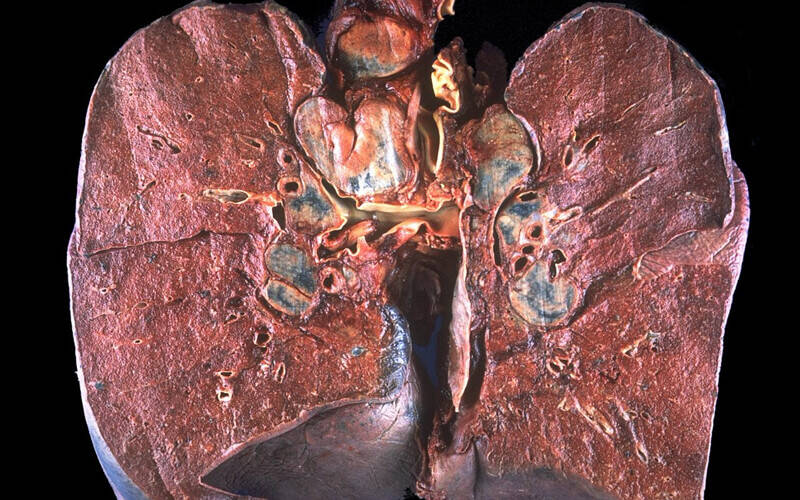

Slika prikazuje granulome i lezije na plućima

(Klikni za uvećanje slike)